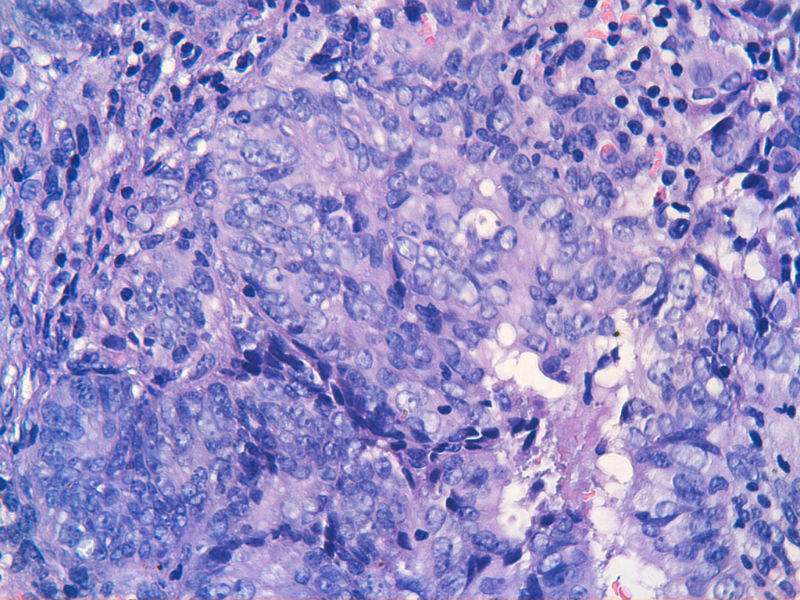

子宫内膜EIN?

图13是做为正常对照的,图7、8、9、12显示的核大小不一,空泡状,形状不规则。女,48岁,宫血半年

子宫内膜呈增生期改变伴局灶区域腺体密集核异性够EIN.

病灶太小,异型不够,需要结合年龄和临床所见,非典要慎重,当心临床过度治疗~~~~